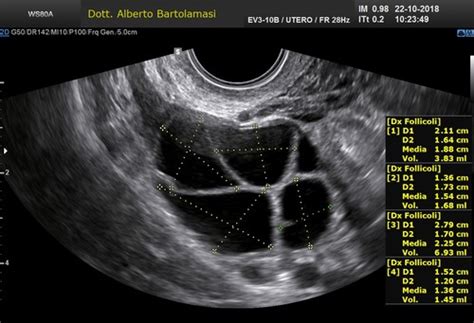

Il medico esegue delle ecografie di controllo per valutare l’aspetto ecografico e lo spessore endometriale. L’ideale sarebbe ottenere un endometrio trilaminare, aspetto tipico della fase periovulatoria della donna in cui nella parte interna dell’utero si osserva un’immagine che riproduce 3 bande, e di spessore superiore a 7 millimetri. La crescita dell'endometrio della ricevente viene controllata mediante ultrasuoni fino a raggiungere lo spessore dell'endometrio adatto al trasferimento, che dovrebbe essere compreso tra 7 e 10 mm. Se necessario, il ginecologo può regolare la dose di farmaci ormonali durante il ciclo.

Riuscire ad avere un buono spessore endometriale è una delle questioni più controverse per le pazienti che ricevono ovuli in donazione. Lo spessore dell’endometrio e il suo aspetto ecografico sono due variabili che sono state ampiamente discusse in una moltitudine di articoli. Noi medici abbiamo ancora opinioni diverse sul modo migliore di riuscire ad avere un buon endometrio per il transfer embrionale. Una revisione Cochrane recente conclude che non esiste un protocollo ideale: estradiolo in pillole o cerotti, progesterone vaginale o intramuscolare, agonisti della GnRH o previ per evitare l’ovulazione spontanea. Tutti gli studi mostrano risultati simili. E come succede nella maggior parte dei casi, si raccomanda di realizzare degli studi aggiuntivi per arrivare ad avere dei risultati significativi.

Per quanto riguarda i valori limite per decidere se cancellare o meno un ciclo, ci sono opinioni contrastanti. In primo luogo, perché alcuni aspetti come il pattern ecografico dell’endometrio sono abbastanza soggettivi, e in secondo luogo perché fino al momento non esiste nessuno studio che dimostri qual è lo spessore minimo o massimo che permetta di fare una previsione sul risultato del trattamento (bisogna tenere in considerazione che in questi casi uno spessore maggiore non sempre è migliore). Esistono studi condotti da importanti gruppi di ricerca che hanno scoperto che anche con un endometrio di 4mm si possono ottenere gravidanze normali. Questo porta a una certa confusione tra le pazienti, specialmente quelle che vengono da altri paesi per realizzare il ciclo di ovodonazione. In questi casi, la raccomandazione è sempre la stessa: l’équipe che segue la paziente ha lo stesso interesse che ha la paziente di riuscire ad ottenere un buon risultato, quindi si deve avere completa fiducia nello specialista.

Valutazioni approfondite pre-trattamento e protocolli personalizzati sono cruciali per risultati di successo nella donazione di embrioni. Questo include non solo la preparazione endometriale e la gestione immunologica, ma anche l'analisi di altre condizioni preesistenti nella ricevente. Ad esempio, in un caso di una donna con Tiroidite di Hashimoto trattata con Eutirox, il monitoraggio ecografico ha mostrato un endometrio trilaminare adeguato e i livelli di TSH sono stati stabilizzati con dosaggi aggiustati di Eutirox prima del trasferimento, dimostrando l'importanza di un approccio olistico e personalizzato. L'esame istologico che ha mostrato iperplasia ghiandolare semplice, trattata con terapia progestinica, sottolinea ulteriormente la necessità di affrontare ogni aspetto della salute uterina prima del transfer.